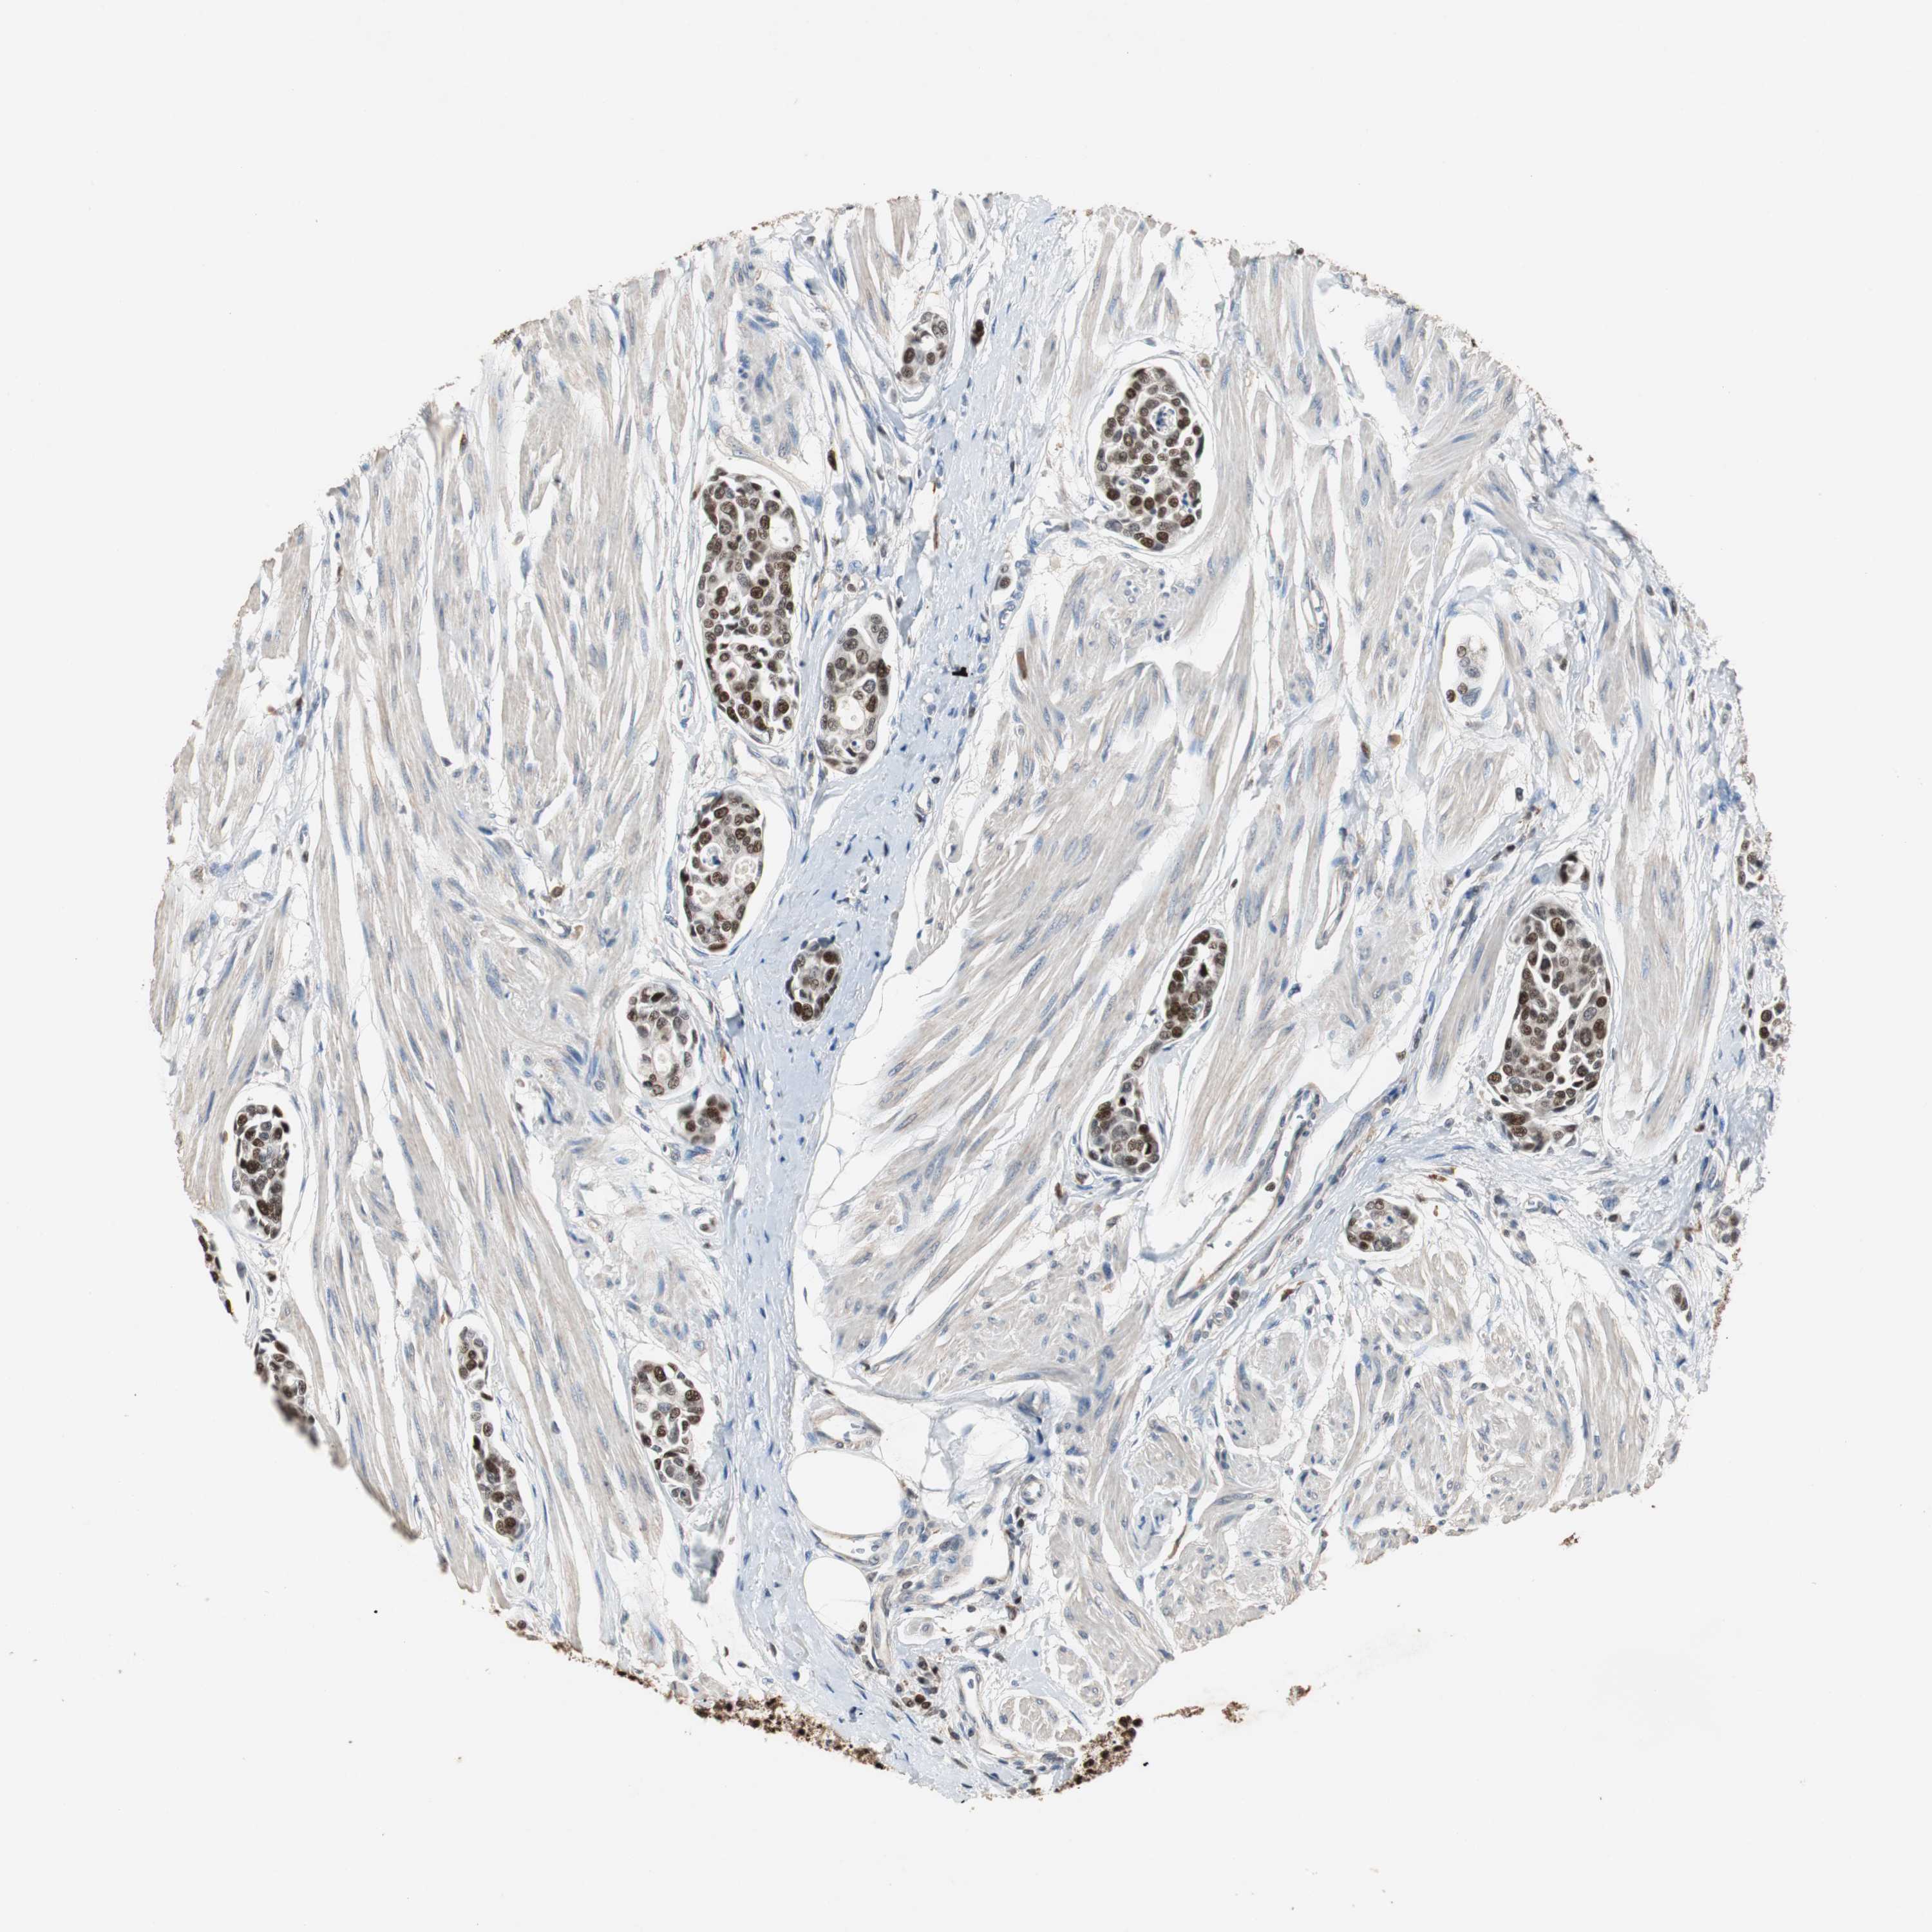

UROTHELIAL CANCER - Protein expressioni

A mouse-over function shows sample information and annotation data. Click on an image to view it in a full screen mode. Samples can be filtered based on level of antibody staining by selecting one or several of the following categories: high, medium, low and not detected. The assay and annotation is described here.

Note that samples used for immunohistochemistry by the Human Protein Atlas do not correspond to samples in the TCGA dataset.

Antibody stainingi

Antibody staining in the annotated cell types in the current human tissue is reported as not detected, low, medium, or high, based on conventional immunohistochemistry profiling in selected tissues. This score is based on the combination of the staining intensity and fraction of stained cells.

Each image is clickable and will lead to virtual microscopy that enables deeper exploration of all samples and also displays staining intensity scores, fraction scores and subcellular localization as well as patient and tissue information for each sample.

Antibody HPA006748

Antibody CAB002262

Staining

High

Medium

Low

Not detected

Intensity

Strong

Moderate

Weak

Negative

Quantity

>75%

75%-25%

<25%

None

Location

Nuclear

Cytoplasmic/membranous

Cytoplasmic/membranous,nuclear

Urothelial carcinoma, Low grade